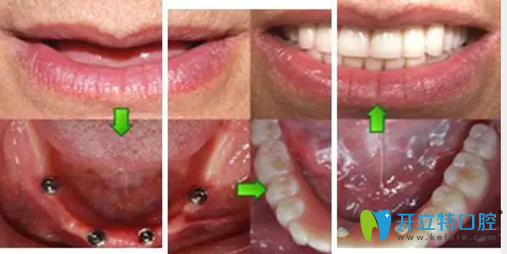

All-on-4種植牙種植過程圖:

鎮(zhèn)江拜博口腔萬書健All-on-4種植牙種植過程圖

萬書健院長給郭先生推薦的是“All-on-4種植牙”,它是利用4顆種植體,1次完成口腔種植修復,一番詳細交流之后,當天就決定種牙。萬院長一邊在電腦上給他演示種牙的位置、顆數(shù),一邊給他分析這樣設(shè)計的優(yōu)勢和好處。

術(shù)后結(jié)束后,郭先生看著整齊的牙齒,笑得合不攏嘴,他說,有了牙,我就有了好胃口,胃口好了,我就能安心享受晚年的生活啦!